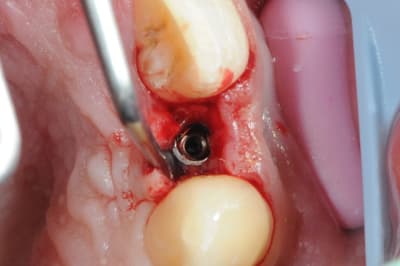

-cicatrisation de la première vis de cica,

-diamètre plus gros pour la vis de cica

- pilier pour la provisoire

- provisoire moule ION

- ajustage

- polissage soigneux

la suite tout à l'heure, ça sonne à la porte...